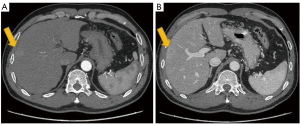

The 55-year-old man, was feeling pain and discomfort in the liver area for several months and had no obvious related medical history. The patient was infected by chronic hepatitis B virus for decades and has not received regular antiviral therapy. Through pre-hospital ultrasound and CT scans, he was preoperatively diagnosed with a space-occupying liver lesion. Before the operation, we carried out the regular antiviral treatment and liver protection drug treatment for the patient for nearly a week. Pre-surgery laboratory test results showed that at 77.9 ng/mL, the concentration of tumor marker alpha-fetoprotein (AFP) was higher than normal limits (Table 1). Liver function indexes were in normal range, whereas ICG retention at 15 minutes (ICG-R15) was 18.9%, which was beyond 15%, indicating that liver metabolism was impaired. Therefore, our assessment was that this patient could only undergo hepatic lobectomy with preoperative tumor localization by computed tomography (CT) (Figure 1). We used an ICG-NIRF imaging system endowed with a qualitative detection limit of 0.488 nM and a quantitative detection limit of 3.91 nM (Figure 2) to observe the tumor and attempt to identify any other tiny tumors in the residual liver. The patient, who had not previously undergone a surgery of this type, was first injected with ICG (0.577 mg/kg ICG) intravenously. However, due to the patient’s impaired metabolism, the surgery was rescheduled for 4 days after the ICG injection in order to obtain an optimal tumor-to-background ratio. The fluorescence signal that emitted from the liver surface could be detected through the NIRF system and could also be clearly recognized when the specimen was analyzed in vitro (Figure 3). After the clear lesion was removed, we observed no residual lesions during the operation. It may due to the shape of the liver cirrhosis nodules affected our judgment. We subsequently tested the residual liver surface with the NIRF system and observed a high signal point of about 1 mm in the right anterior lobe of the liver, which showed no differences from normal liver through naked-eye observation and palpation. In our previous case, no result showed the NIRF system can detect lesions smaller than 1cm, and due to the limitations of fluorescence technology, it is impossible to determine whether it was an inflammatory tissue, but the high intensity of fluorescence raised our suspicions. After excision, the specimen also sustainably expressed high fluorescence (Figure 4). Finally the histopathological examination revealed that this tiny fluorescent spot belong to a single focus of an early HCC (Figure 5). On the histopathological images, steatosis and Mallory-Denk bodies were identified. Meanwhile, multinucleation and nuclear atypia were also detected, displaying nuclear overlapping, size enlargement, and nuclear membrane distortion. The surgery lasted 235 minutes and intraoperative bleeding was 200 mL. The patient had good compliance and no discomfort was reported following the surgery. The follow-up of the patient was done through periodic CT scans and AFP-level testing to further assess the HCC prognosis. The patient’s liver function and AFP were close to normal before discharge. So far, no tumor recurrence has been found in the follow-up.